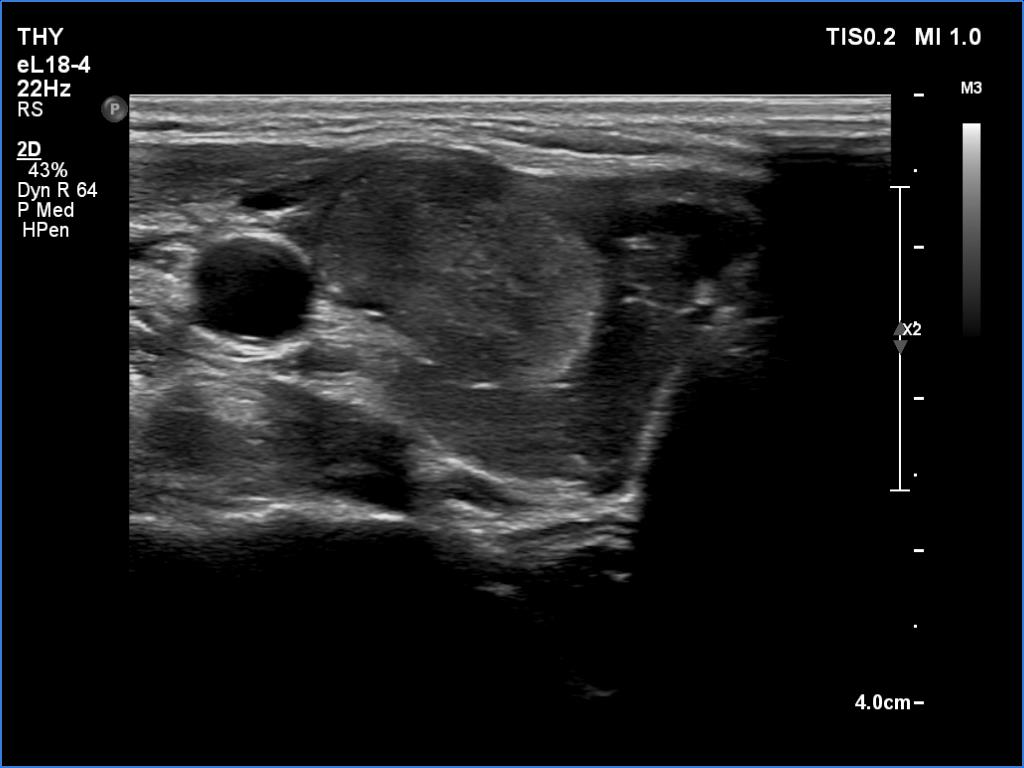

Ultrasonography. The thyroid was hypoechoic. The right lobe had a heterogeneous, dominantly minimally/moderately hypoechoic nodule in the ventrolateral part which had irregular borders and both perinodular and intranodular vascularity. There was another, hyperechoic star-like lesion in the central part of the right lobe. This lesion presented microcalcifications and was avascular. The left lobe was homogeneously hypoechoic.